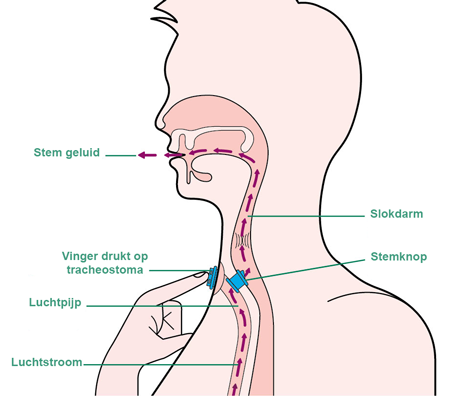

Larynxkanker treft voornameljk mensen boven de 50 jaar. De patiënten ondervinden heel wat hinder om zich na de operatie verstaanbaar te maken. Het aanleren van de slokdarmspraak, het spreken met een stemknoopje of met een Servox vergt heel wat oefening van de patiënt en dient begeleid te worden door een logopedist(e).

De patient zal opnieuw moeten leren praten.

Vlak na de operatie kan de patiënt niet meer praten. Maar vóór de patiënt het ziekenhuis verlaat gaat de logopedist(e) hem/haar de eerste woordjes leren spreken. En dan kan het vlug gaan. De patiënt kan leren spreken met een vervangstem via verschillende revalidatiemethodes.

En sinds het spreekknoopje automatisch geplaatst wordt, leert bijna iedereen terug spreken.